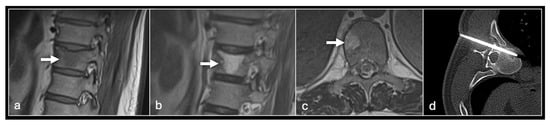

Figure 3. Sagittal T1 (a), T2 (b) and axial T2 (c) showing tumour (arrow) in the vertebral body and CT guided biopsy of the lesion (d).

Bone lesion biopsy is a similarly variable process. However, given that such lesions are almost invariably deep and typically have either a calcified component or lie behind a bony cortex, ultrasound is usually not a feasible option. Therefore, CT guidance is the workhorse of these procedures in our centre. As with soft tissue lesions, an initial planning scan is followed by local anaesthetic administration and then ‘CT fluoroscopy’ imaging as a percutaneous biopsy system is targeted to the lesion.

We use two main needle systems. Most bone lesions can be sampled with a T-Lok eight-gauge system with an inner diamond-tipped stylet and outer cannula. This is inserted through the cortex overlying a bone lesion. Once in the lesion, the stylet is removed and the cannula is advanced to the deep wall of the lesion aiming to trap the core against normal bone on either side. A tray is then inserted through the cannula to acquire the sample. Both tray and cannula are withdrawn together and the sample is then deposited into the relevant histopathology or microbiology pots (Figure 2 and Figure 3). Typically, only one sample is needed unlike in a soft tissue biopsy.